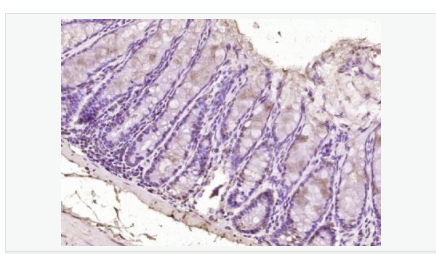

交叉反應:Human,Mouse(predicted:Rat,Dog,Pig,Cow,Rabbit) 推薦應用:IHC-P,IHC-F,ICC,IF,ELISA

產品應用ELISA=1:5000-10000 IHC-P=1:100-500 IHC-F=1:100-500 ICC=1:100-500 IF=1:100-500 (石蠟切片需做抗原修復)

Widely expressed in adult and fetal tissues. Present both in mesenchymal and epithelial cells in some adult tissues, including colon. Tends to be down-regulated in prostate adenocarcinomas and colorectal tumors due to promoter hypermethylation.